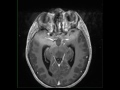

Tectal Plate Glioma

12-year-old male with chronic headaches. There is an infiltrative T1-hypointense mass centered on the tectal plate and periaqueductal gray matter of the midbrain resulting in complete effacement of the cerebral aqueduct. The lesion is FLAIR-hyperintense, and extends rostrally into the left greater than right thalami. There is also extension into the left mesial temporal lobe, including the hippocampus. There is no enhancement within the mass. There is mild supratentorial hydrocephalus secondary to the aqueductal obstruction. The findings are compatible with a tectal plate glioma. Gliomas of the brainstem can be subcategorized into two classes. The first class consists of infiltrative pontine lesions, which are rapidly progressive. The second category includes more well defined gliomas of the midbrain, tectum, and medulla. The latter class are more indolent in nature. Tectal gliomas are infamous for causing obstructive hydrocephalus, even at a relatively small size. There may be both cystic and enhancing components.